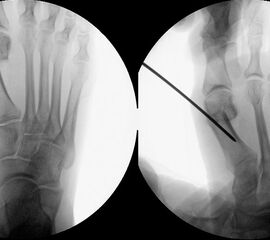

Abbildung 1

• Korrekturpotential größer als beim offenen Chevron, da die Gelenkkapsel als stabilisierendes Element erhalten bleibt und über eine trikortikale Osteosynthese mit zwei kanülierten Schrauben eine Verschiebung bis ca. 80% des Metatarsaledurchmessers möglich ist (Abb. 1).